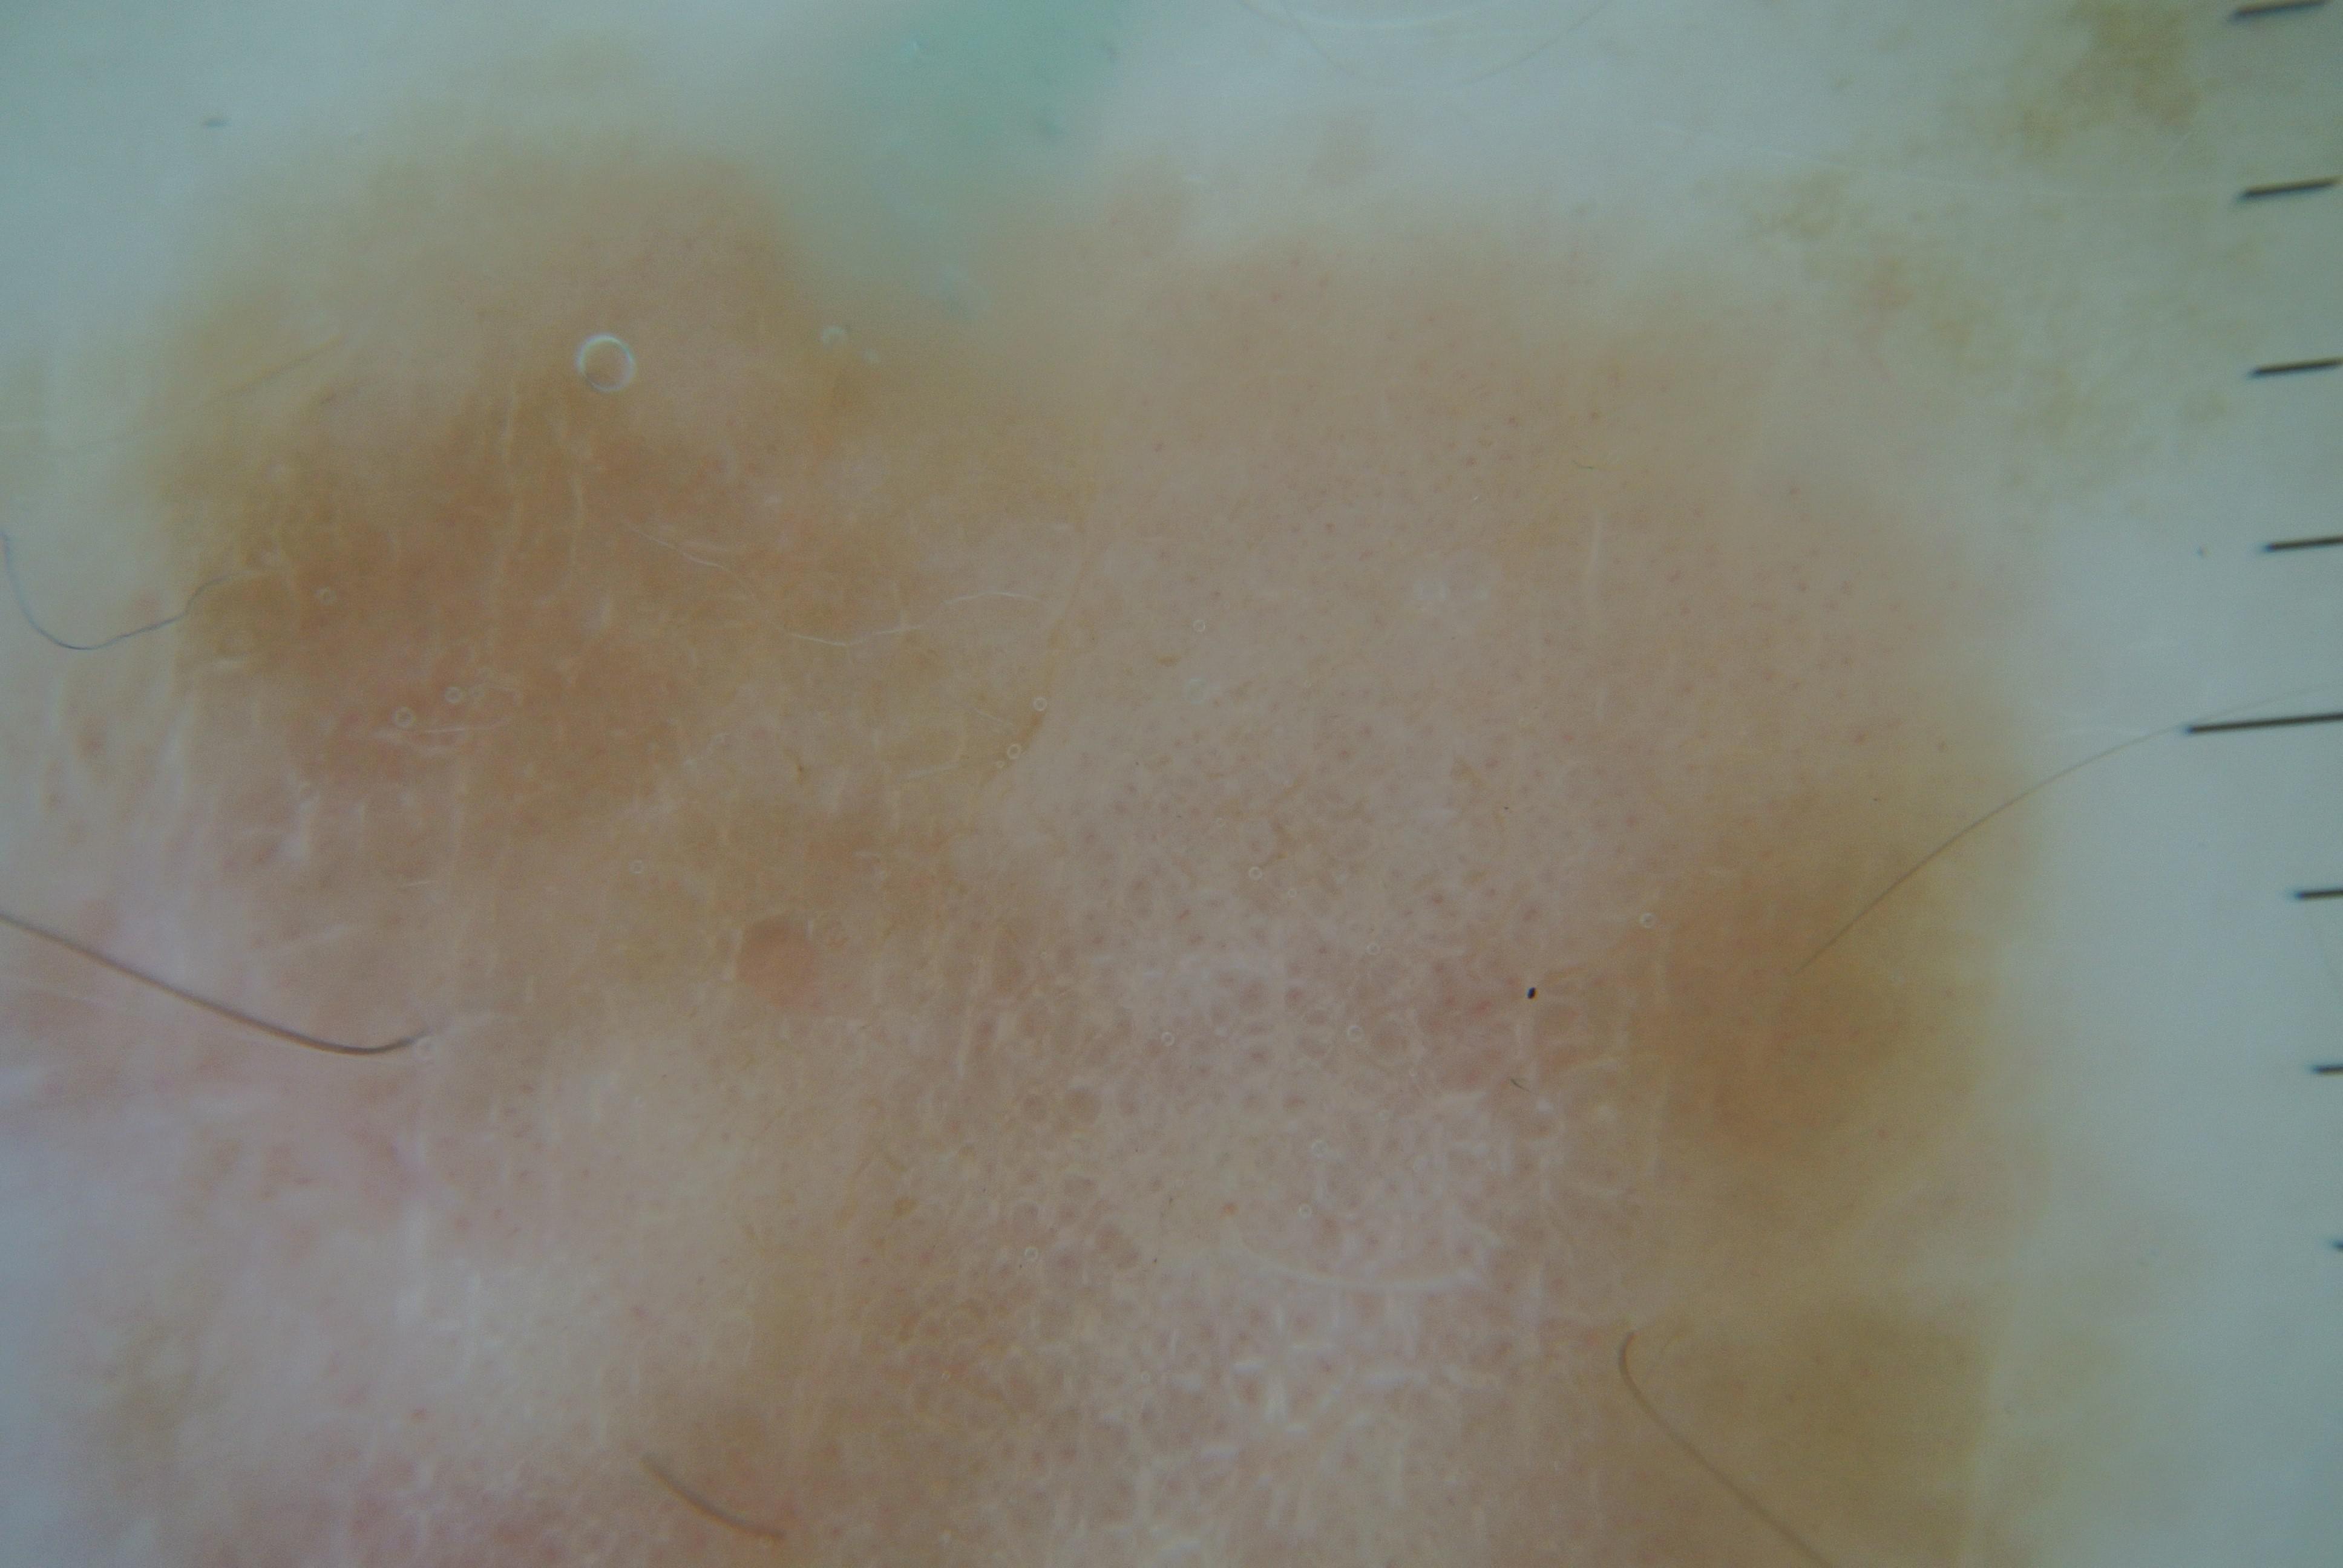

{

"age_approx": 65,

"anatom_site_general": "anterior torso",

"concomitant_biopsy": true,

"dermoscopic_type": "contact polarized",

"diagnosis_1": "Malignant",

"diagnosis_2": "Malignant melanocytic proliferations (Melanoma)",

"diagnosis_3": "Melanoma in situ",

"diagnosis_confirm_type": "histopathology",

"family_hx_mm": false,

"image_type": "dermoscopic",

"mel_thick_mm": "0.00",

"melanocytic": true,

"patient_id": "IP_4465811",

"personal_hx_mm": true,

"sex": "male"

}